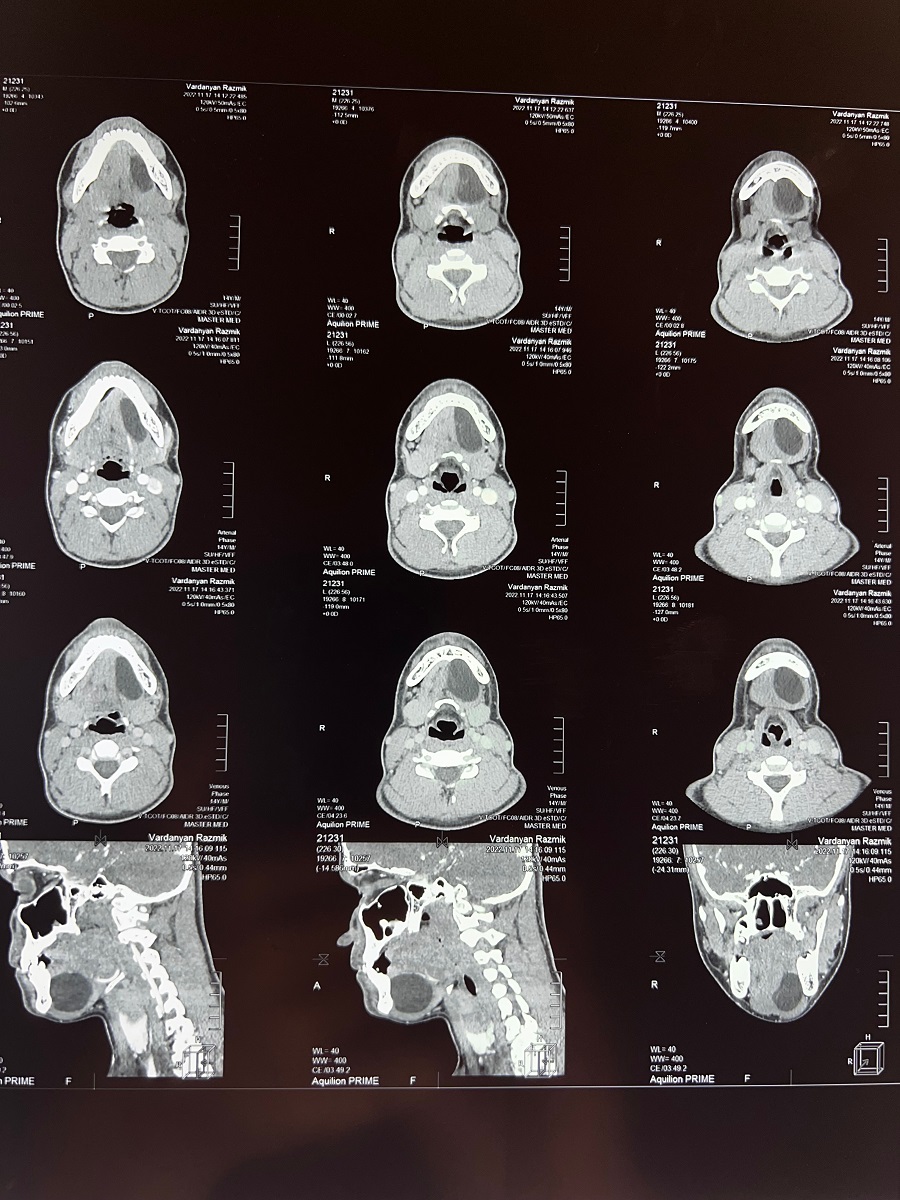

Դիմել են «Մուրացան» համալսարանական հիվանդանոց, կատարված հետազոտությունների արդյունքում ախտորոշվել է պարանոցի միջային հատվածի գոյացություն՝ դերմոիդ բուշտ: